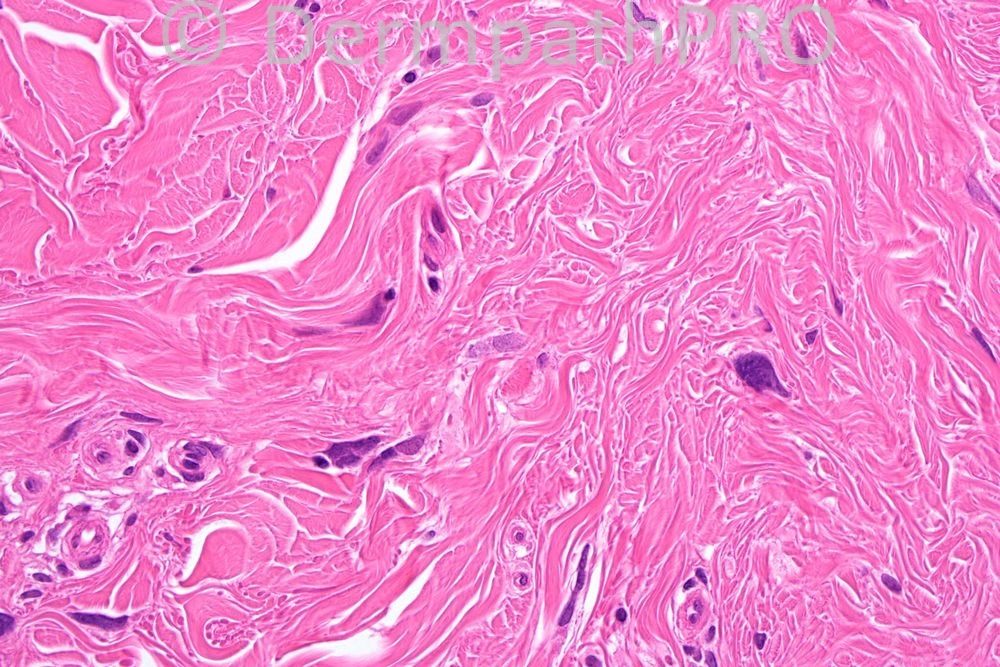

Female 56 years, nodule on upper arm.

Well done everyone! The diagnosis was Pleomorphic fibroma. See you tomorrow.